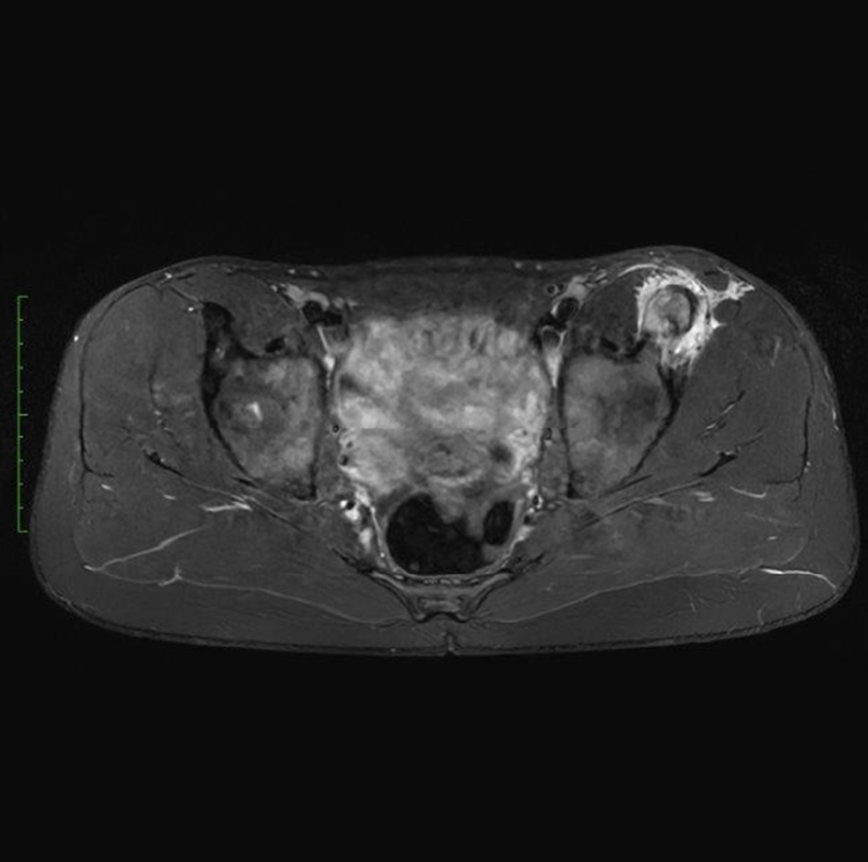

La velocità di progressione della fibrosi cardiaca: un nuovo orizzonte

La velocità di progressione della fibrosi cardiaca emerge come un nuovo e cruciale indicatore prognostico nella cardiomiopatia ipertrofica. Un recente studio evidenzia come l’LGE rate sia più predittivo degli eventi avversi rispetto alla semplice estensione della fibrosi, aprendo nuove prospettive per il monitoraggio e la gestione terapeutica dei pazienti.